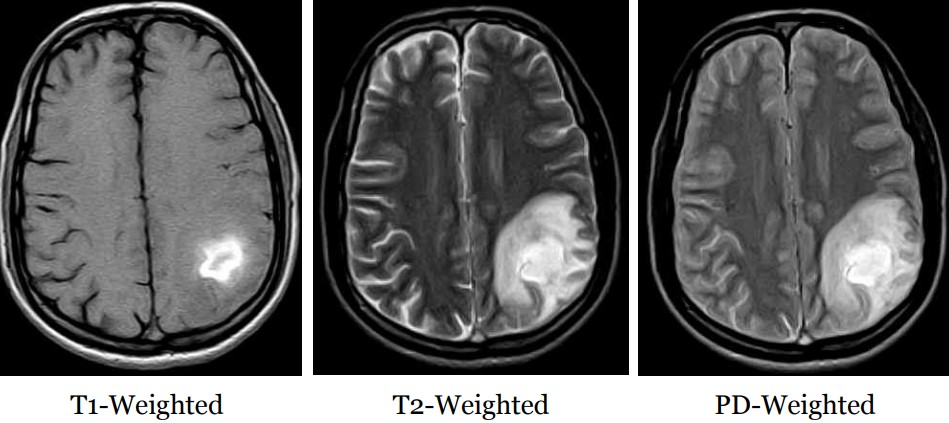

Differences Between T~1~ and T~2~ Weighted Images

Figure 13.18: Differences Between T1 and T2 Weighted Images

Both of the above images can be used to diagnose any abnormalities that may be in the patient.